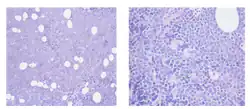

.png)

One combination for stage III/IV relapsed or refractory indolent lymphomas and mantle cell lymphoma (MCL), with or without prior rituximab-containing chemoimmunotherapy treatment, is bendamustine with mitoxantrone and rituximab.[8] In Germany in 2012 it has become the first line treatment of choice for indolent lymphoma.[9] Trial results released in June 2012 showed that it more than doubled disease progression-free survival when given along with rituximab. The combination also left patients with fewer side effects than the older R-CHOP treatment.[10]